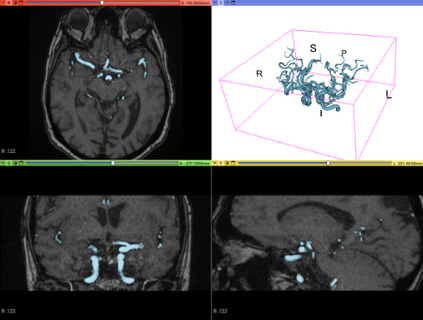

We hereby present a full synthetic model, able to mimic the various constituents of the cerebral vascular tree: the cerebral arteries, the bifurcations and the intracranial aneurysms. By building this model, our goal was to provide a substantial dataset of brain arteries which could be used by a 3D Convolutional Neural Network (CNN) to either segment or detect/recognize various vascular diseases (such as artery dissection/thrombosis) or even some portions of the cerebral vasculature, such as the bifurcations or aneurysms. In this study, we will particularly focus on Intra-Cranial Aneurysm (ICA) detection and segmentation. The cerebral aneurysms most often occur on a particular structure of the vascular tree named the Circle of Willis. Various studies have been conducted to detect and monitor the ICAs and those based on Deep Learning (DL) achieve the best performances. Specifically, in this work, we propose a full synthetic 3D model able to mimic the brain vasculature as acquired by Magnetic Resonance Angiography (MRA), and more particularly the Time Of Flight (TOF) principle. Among the various MRI modalities, the MRA-TOF allows to have a relatively good rendering of the blood vessels and is non-invasive (no contrast liquid injection). Our model has been designed to simultaneously mimic the arteries geometry, the ICA shape and the background noise. The geometry of the vascular tree is modeled thanks to an interpolation with 3D Spline functions, and the statistical properties of the background MRI noise is collected from MRA acquisitions and reproduced within the model. In this work, we thoroughly describe the synthetic vasculature model, we build up a neural network designed for ICA segmentation and detection, and finally, we carry out an in-depth evaluation of the performance gap gained thanks to the synthetic model data augmentation.